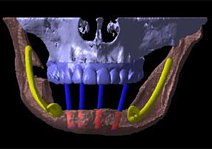

実際にCTで撮影し、「CTデータ3D立体構築画像変換検査」したものがどう見えるのがご覧下さい。CTデータ3D立体構築画像変換検査した場合、3次元でどこにどのようにインプラントを埋め込んでいけばいいのか、立体的に把握することができます。

CTデータ3D立体構築画像変換検査は患者さまの顎の骨や歯の状況を立体的に把握します。あらゆる角度から検討でき、インプラントの植え込み位置、角度などの事前シミュレーションが的確に行われ、数値化することができます。

吉本歯科医院でインプラント治療を行う患者さまの顎の状態は、CT画像だけでなくここまで立体化されたものが手術前には手元にあり、シミュレーションを行ってから実際の手術に入るような流れをとっております。

CTデータ3D立体構築画像によりシミュレーションしたインプラントの埋入位置を高精度に反映した手術用テンプレートを作製します。

手術前に「どこの位置に、どの角度で、どの深さで」などといった細かいシミュレーションが行えます。

また、逆に言うとこのサージカルガイドにより、失敗しようがないほど正確な位置へインプラントの埋入を行なうことができます。

顎の模型とサージカルガイド

顎の模型とサージカルガイド

顎の模型にサージカルガイドをセットしたところ

顎の模型にサージカルガイドをセットしたところ

従来の、開けてみてからどのあたりまで入れるかを歯科医師の感覚で決める、といったリスクの大きい治療とは根本から考えが異なるものです。